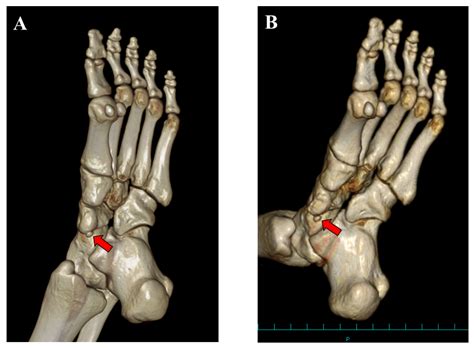

There are three main types of accessory navicular bone, classified based on their structure and connection to the navicular bone:

Type Description

Type I A small, round bone connected to the navicular bone by a fibrous or cartilaginous structure. This type is often asymptomatic.

Type II A larger, triangular bone connected to the navicular bone by a fibrous or cartilaginous structure. This type is more likely to cause symptoms.

Type III A large, triangular bone that is fused to the navicular bone. This type is often asymptomatic but can cause symptoms if there is inflammation or irritation.

• Imaging Tests: X-rays, MRI, or CT scans may be ordered to visualize the accessory navicular bone and assess its structure and connection to the navicular bone.

These diagnostic tools help determine the type of accessory navicular bone and the extent of any associated symptoms.